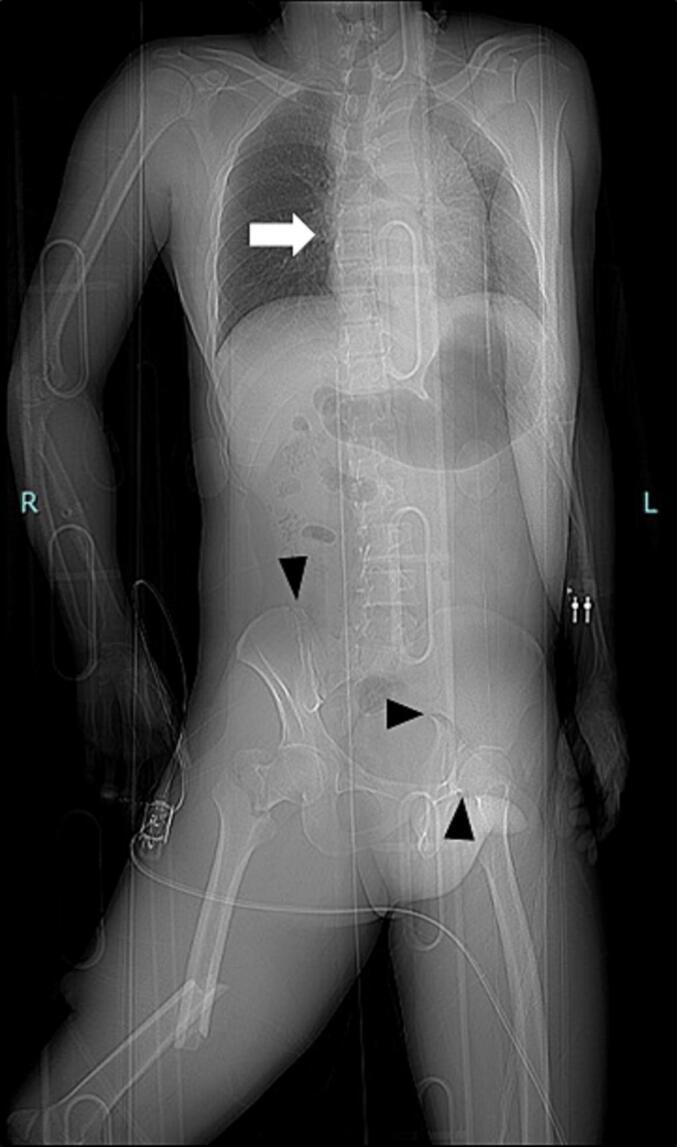

A 35-year-old man sustained multiple injuries after a motor vehicle accident and was transferred to our hospital in shock status. CT revealed a grade IV BTAI rupturing into the thoracic cavity and pelvic fracture. Soon after preperitoneal pelvic packing and transcatheter arterial embolization for pelvic fracture, TEVAR was performed in the hybrid ER without transporting the patient. The patient was transferred to a rehabilitation hospital on postoperative day 41.

一名35岁男性在机动车事故后多处受伤,以休克状态被转送至我院。CT显示为IV级BTAI,破裂进入胸腔且伴有骨盆骨折。在对骨盆骨折进行腹膜前骨盆填塞和经导管动脉栓塞后不久,患者在混合型急诊室内接受了TEVAR治疗,未进行转运。患者于术后第41天转至康复医院。